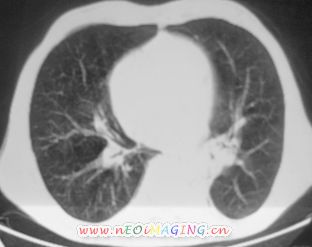

以下是引用卜一在2007-10-7 9:38:00的发言:[br]左下肺胸膜下团片影,内见含气支气管像,临近胸膜未见增厚。多考虑:1 左下肺炎症,建议消炎后复查!2 不除外肺隔离症合并感染!